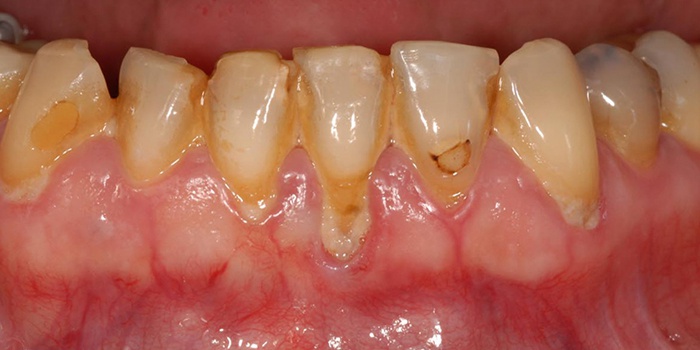

Якщо у вас почали кровоточити ясна, то це може бути першим симптомом пародонтозу. Це хворобливий стан, викликаний процесами атрофії тканин, причина яких поки не встановлена. Як лікувати пародонтоз правильно? Давайте розберемося, що таке пародонтоз і як його лікувати за сучасним стоматологічним розробок. Дізнаємося, як позбутися від хвороби засобами народної медицини, які необхідні заходи профілактики цієї недуги, до якого фахівця звертатися.

Вибір тактики лікування пародонтозу залежить від стадії розвитку захворювання, ступеня ураження ясен та кісткової тканини. Стоматолог визначає, наскільки великий запальний процес, яка кількість зубів вже не підлягає відновленню, а потім складає комплексну програму, віддаючи перевагу певним методам лікування. Як лікують пародонтоз в клініках? Алгоритм лікарських маніпуляцій виглядає наступним чином: